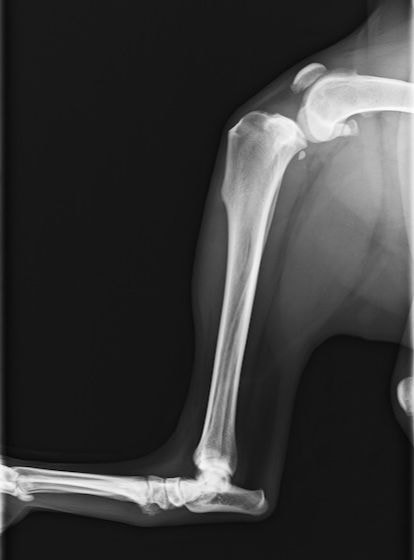

バーニーズマウンテンドック 4歳 避妊♀

突然の右後肢跛行を主訴に来院されました。整形外科学的検査において右膝に脛骨圧迫テストで陽性、前方引き出し徴候が認められました。神経学的検査において特に異常は認められませんでした。レントゲン検査において、関節液の貯留所見や脛骨の前方変位の所見が認められました。

関節鏡検査を実施いたしました。関節鏡検査では、重度の滑膜炎および前十字靭帯の完全断裂が認められました。半月板に損傷は認められませんでした。

断裂前十字靭帯の除去を行いました。その後 TTA(Tibial tuberosity advancement)を実施しました。

術後経過は良好で、後肢機能・筋肉量の改善目的で現在はリハビリテーションを行っています。